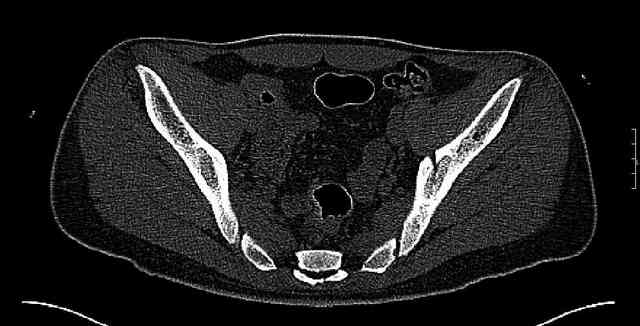

The last two images from the 3-D CT scan certainly makes the fracture look worse than the plan radiographs.

The joint is non-concentric as the head appears to be either "following the caudal segment", or the dome component is displaced from the tethered head... or so it seems... and he's young... so, many fracture surgeons would recommend reduction and fixation.

So we must decide preoperatively which part is the displaced segment?

It's difficult to know from these few selected images which component of the injury (was before and now) should be deemed the "soon to be mobile"

segment. It's my best guess that it is the caudal portion and there exists a healing fracture line somewhere thru the posterior column...one image

suggests it. If true, its early healing/union should be disrupted, and the resultant fragment mobility then allows accurate reduction.

Some more images. Does it help to guess which part of the acetabulum is displaced?